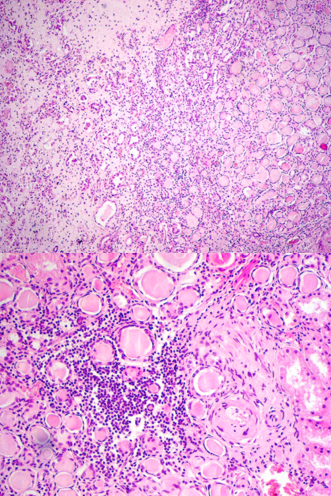

identify

Necrosis papillarum renalium (366)